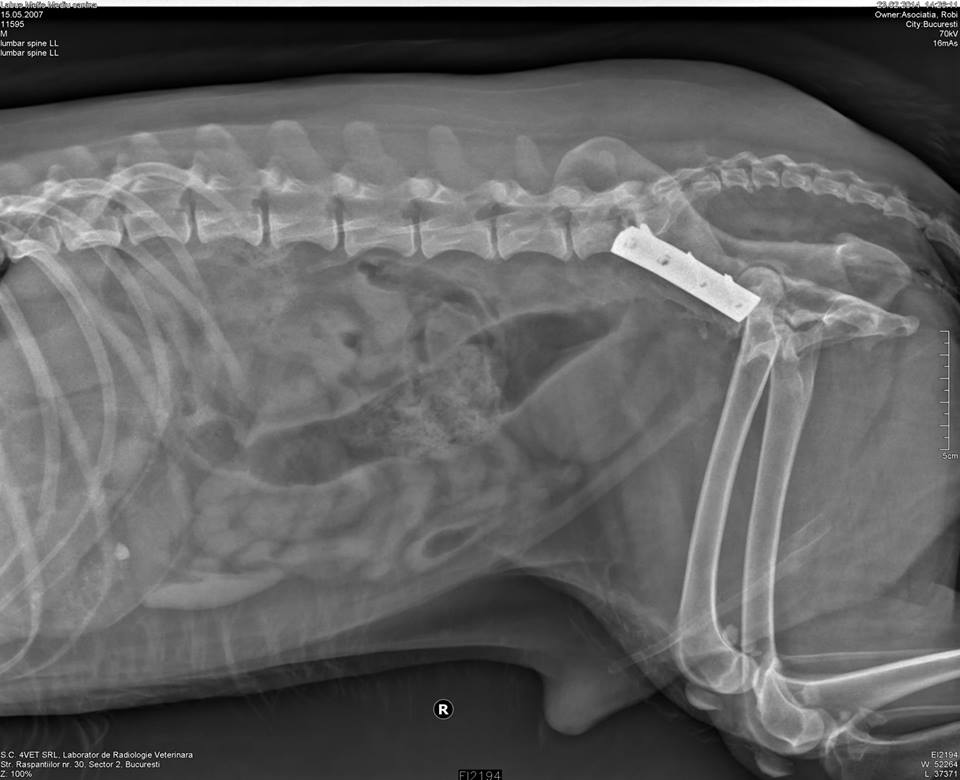

Din pacate, dupa ce va termina tratamentul cu antibiotic, va fi nevoie de o interventie pentru eliminarea placutei metalice. Unul din suruburi preseaza intestinul (o alta cauza a constipatiei) si mentine infectia ‘anuala’ a piciorului.

Unfortunately, after the antibiotics treatment, Labus must undergo a surgery to remove the metal plate in his leg. One of the screws is pressing on the intestine (also causing constipation) and maintains the leg infection.